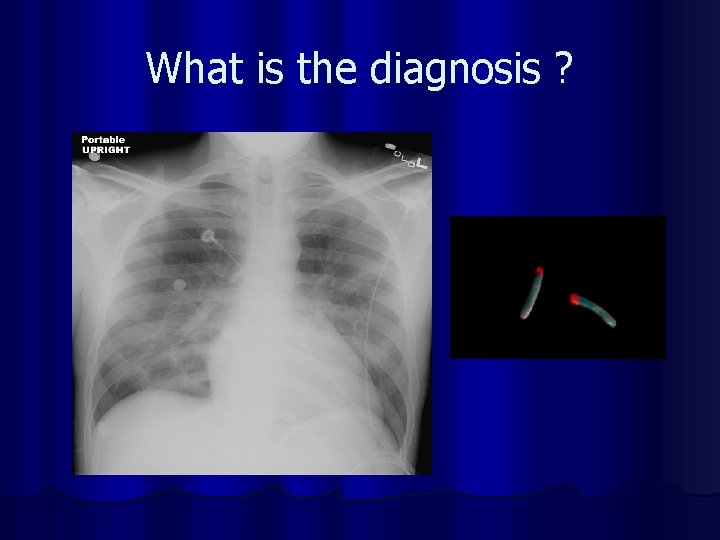

Which lobe is involved l What is the organism l

l 60 years old woman is brought to hospital in confusional state. She is febrile and short of breath. On auscultation there are few crackles in the mid zone bilaterally. She is anaemic. WBC count is 6 X 109. l Her chest x-ray is :

What is the diagnosis ?

Mycoplasma Pneumonia)

Legionella Pneumonia